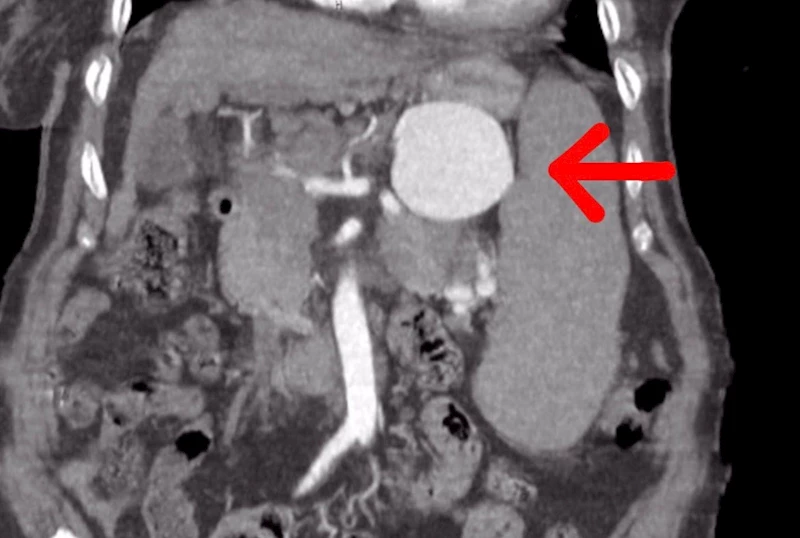

Şırnak’ta, Kalp ve Damar Cerrahisi Uzmanı Op. Dr. Volkan Burak Taban ve Genel Cerrahi Uzmanı Op. Dr. Serhat Binici, dalak arterinde oluşan 7 santimlik baloncuğu yaptıkları riskli ameliyatı başarı ile tamamlayarak 75 yaşındaki ve kronik birçok hastalığı olan Ayşe Ertur’u sağlığına kavuşturdu.

Mardin, Diyarbakır, Batman, Siirt, Gaziantep ve Şanlıurfa gibi birçok hastanede dalağının alınması gerektiği ancak dalağının alınması halinde de ameliyat masasından kalkamayacağı söylenen 75 yaşındaki Ayşe Ertur, birçok kronik rahatsızlığına rağmen Şırnak Devlet Hastanesi’nde geçirdiği başarılı ameliyat ile sağlığına kavuştu.

Yapılan ameliyat ile ilgili gazetecilere açıklamalarda bulunan Op. Dr. Volkan Burak Taban, hastanın gastroenteroloji kliniğinden kendilerine geldiğini, dalak arterinde ciddi bir anerizma şüphesinden bahsedildiğini söyledi. Değerlendirmeler sonrası ilaç tetkikleri istediklerini belirten Dr. Taban, "Yapılan tomografide teyzemizde dalak arterinde oldukça geniş dev diyebileceğimiz anerizmanın yani baloncuklaşmanın olduğunu gördük. Normalde dalak anerizması diyebilmemiz için baloncuklaşma diyebilmemiz için 20 milim yani 2 santimin üstüne çıkması lazım. Ama gördüğümüzde bizde şaşırdık. Çünkü yaklaşık 7 santimi geçen bir dalak anerizması vardı. Hastanın bu anerizmanın içerisinde tamamen kan dolduğu için her an patlama riski vardı. Allah korusun hastanın hayatını kaybetme riski ile de karşı karşıyaydık. Hasta ile ilgili hemen multidisipliner olarak bir değerlendirme yaptık. Hem gastroenteroloji, hem genel cerrahiden Serhat hocamız, hem radyoloji kliniğimiz ile beraber değerlendirme yaptık. Hastamızın 15 yıldır mücadele verdiği bir karaciğer sirozu da bizim kararlarımızda etkili oldu” dedi.

“Hasta Şırnak’ta tedavi olmak istedi”

75 yaşındaki hastanın Şırnak’ta ameliyat edilmesinin riskli olduğunu ve bu durumu hem hastaya hem de hasta yakınlarına söylediklerini aktaran Dr. Taban, "Hastamız ve yakınları yıllardır hastanemizde tedavi olmak istediler. Bizde hastamıza açık cerrahinin ilk etapta riskli olabileceğini düşündük. Çünkü karaciğer sirozuna bağlı ve diğer hastalıklara bağlı olarak kan değerlerinde inanılmaz derecede bir bozukluk vardı ve cerrahi oldukça riskliydi. Biz öncelikle anjiyo yoluyla kasıktan girerek dalak anerizmasına ulaşıp, dalak anerizmasının içerisini kapatmayı ve dalak damarına bir stent koyarak oradaki anerizmanın patlamasını engellemeyi çalıştık. Anjiyomuz yaklaşık 1,5-2 saat sürdü. Anjiyo salonuna aldık hastamızı, anjiyo sırasında ne kadar uğraşsak ta dalak damarı o kadar genişlemişki kendi etrafındaki damarlar ile beraber döndüğü için dalak damarını bir türlü kateterize edemedik. Dalak damarının içerisine ulaşsak da ardına ulaşamadık. Yaptığımız tekrar değerlendirmesinde hastamızın ameliyat edilmesinin daha doğru olacağını düşündük. Hastamızı açık cerrahi vakasına aldık. Açık cerrahi vakasında genel cerrahi ile birlikte, önce karından ufak bir keski ile girdik. Girdiğimizde karşılaştığımız manzara aslında tomografide gördüğümüz manzaradan veya anjiyoda gördüğümüz manzaradan daha da kötü haldeydi. Dalak damarı anerizmasını onararak hastamızı ameliyattan çıkardık. Ameliyat sonrasında da hastamızın bir yoğun bakım ihtiyacı olmadı. Servise aldık. Bundan sonraki değerlerimize baktığımızda da ciddi bir kan ihtiyacı olmadı. Daha sonraki kontrol kanlarımızda gayet iyi olduğu gözüküyor" dedi.